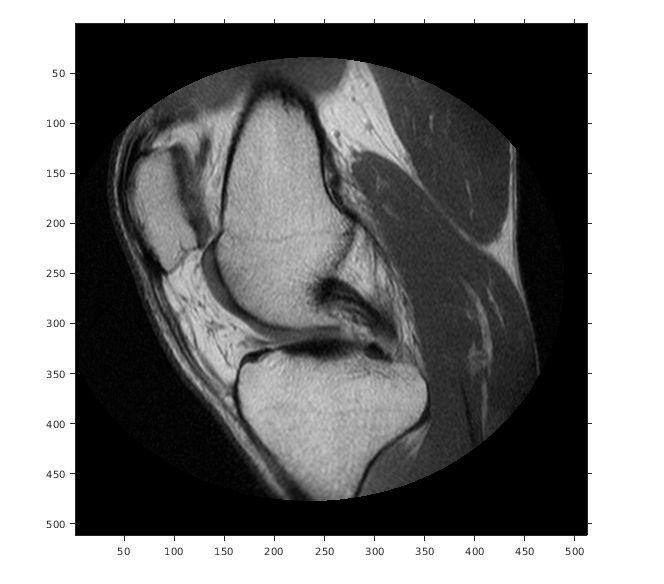

Считайте 2D полутоновое изображение в рабочую область.

m = dicominfo('knee1.dcm');

A = dicomread(m);

Создайте imref2d объект, задавая размер и разрешение пикселей. Файл DICOM содержит поле метаданных PixelSpacing это задает разрешение изображения в каждой размерности в миллиметрах на пиксель.

RA = imref2d(size(A),m.PixelSpacing(2),m.PixelSpacing(1))

RA =

imref2d with properties:

XWorldLimits: [0.1562 160.1562]

YWorldLimits: [0.1562 160.1562]

ImageSize: [512 512]

PixelExtentInWorldX: 0.3125

PixelExtentInWorldY: 0.3125

ImageExtentInWorldX: 160

ImageExtentInWorldY: 160

XIntrinsicLimits: [0.5000 512.5000]

YIntrinsicLimits: [0.5000 512.5000]

Отобразите изображение, не использовав пространственный объект привязки. Координаты осей отражают внутренние координаты. Заметьте, что координата (0,0) находится в левом верхнем углу.

figure

imshow(A,'DisplayRange',[0 512])

axis on

Предположим, что вы хотите вычислить аппроксимированное положение и ширину колена в миллиметрах. Выберите конечные точки линейного сегмента, который запускается горизонтально через колено на уровне коленной чашечки. Например, используйте (x, y) точки (34,172) и (442,172).

xIntrinsic = [34 442];

yIntrinsic = [172 172];

Преобразуйте эти точки от внутренних координат до мировых координат.

[xWorld,yWorld] = intrinsicToWorld(RA,xIntrinsic,yIntrinsic)

xWorld = 1×2

10.6250  138.1250

yWorld = 1×2

53.7500   53.7500

Мировые координаты двух точек (10.625,53.75) и (138.125,53.75) в модулях миллиметров. Аппроксимированная ширина колена в миллиметрах:

width = xWorld(2) - xWorld(1)

width = 127.5000